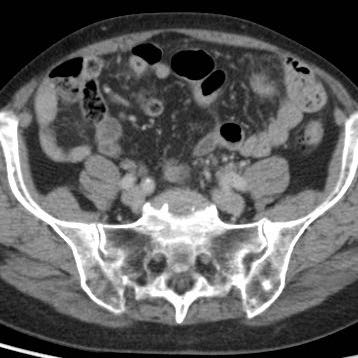

Hai cá nhân không có triệu chứng với ruột thừa kích thước lớn, chứa đầy phân nhưng không viêm, được minh họa qua siêu âm và CT.

Lưu ý sự vắng mặt hoàn toàn của mô mỡ viêm xung quanh ở cả hai trường hợp.